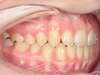

Cas 4 : Description

Chevauchement sévère. Traitement multibague sans extraction.

Avant

Après